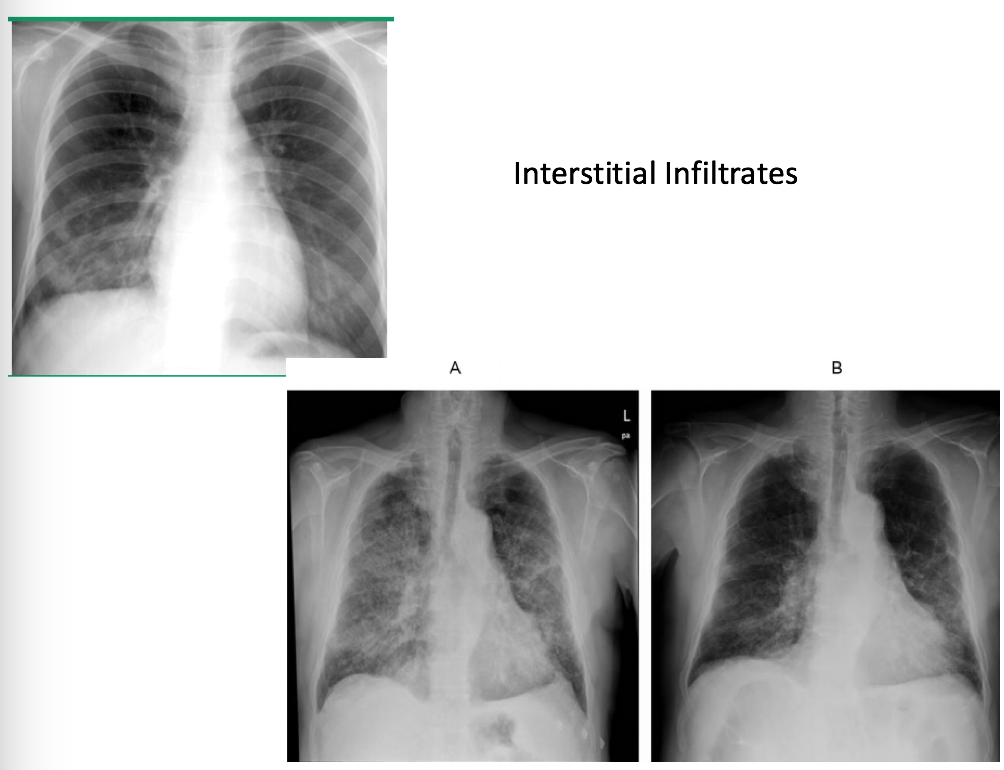

What do you see on CXR in CAP?

Deonstratable infiltrate

What is the gold standard for diagnosing CAP?

CXR